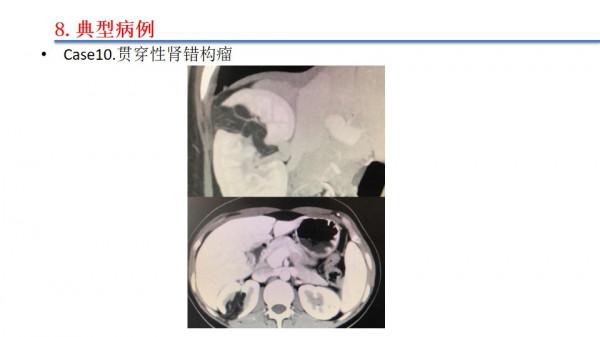

近1年多以來,江偉凡博士完成了50餘例腹腔鏡腎部分切除術,其中多數病例是複雜疑難病例,手術效果均滿意。江偉凡博士將做腹腔鏡腎部分切除術治療複雜腎腫瘤的新進展及病例分享,他把腹腔鏡腎部分切除術的國內外最新進展做了個整理,並挑選了自己診治的10例複雜腎腫瘤病例進行分享。